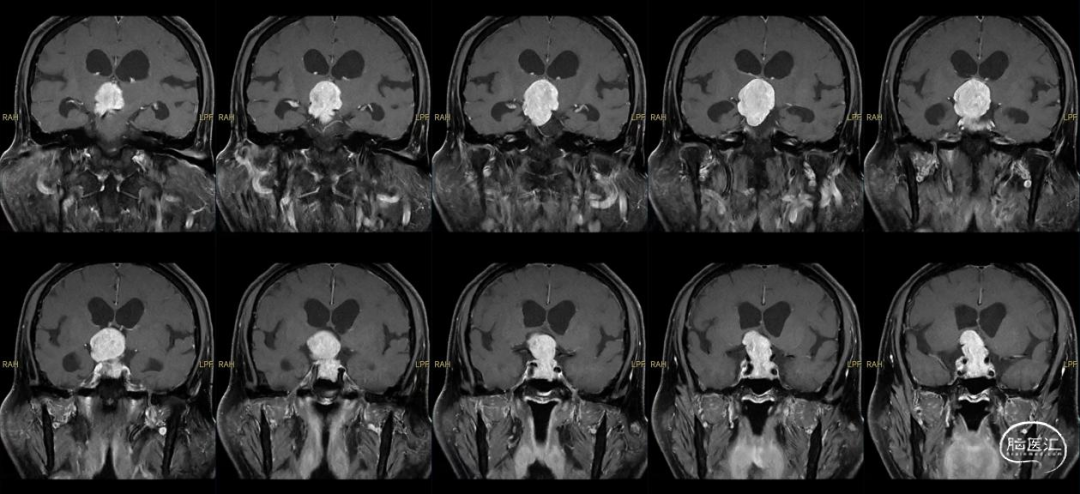

患者主诉:因双眼视物不清进行性加重5年入院。

诊断:鞍区鞍上巨大侵袭性垂体瘤。

5.我科在磁共振复合手术室的支持下,术中充分使用神经导航、术中多普勒超声等辅助技术,经鼻内镜扩大入路切除鞍区鞍上巨大侵袭性垂体瘤;其创伤小、显露清晰、抵近直视下切除肿瘤及保护周围的神经血管及脑组织,减少和避免副损伤,手术效果好,术后恢复快!